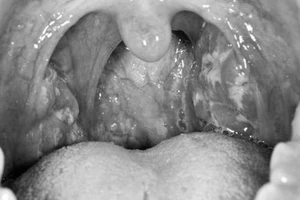

Sau khi cắt amidan có được ăn kem, uống nước ngọt?

(PLO)- Sau khi cắt amidan, để vết mổ nhanh lành và cơ thể mau hồi phục, bạn cần kiêng một số loại thực phẩm và hoạt động mạnh trong vòng 1-2 tuần đầu tiên...

Sau khi cắt amidan, để mau chóng hồi phục tôi cần kiêng ăn những gì và sinh hoạt như thế nào? Có được ăn kem để làm dịu vết thương không?